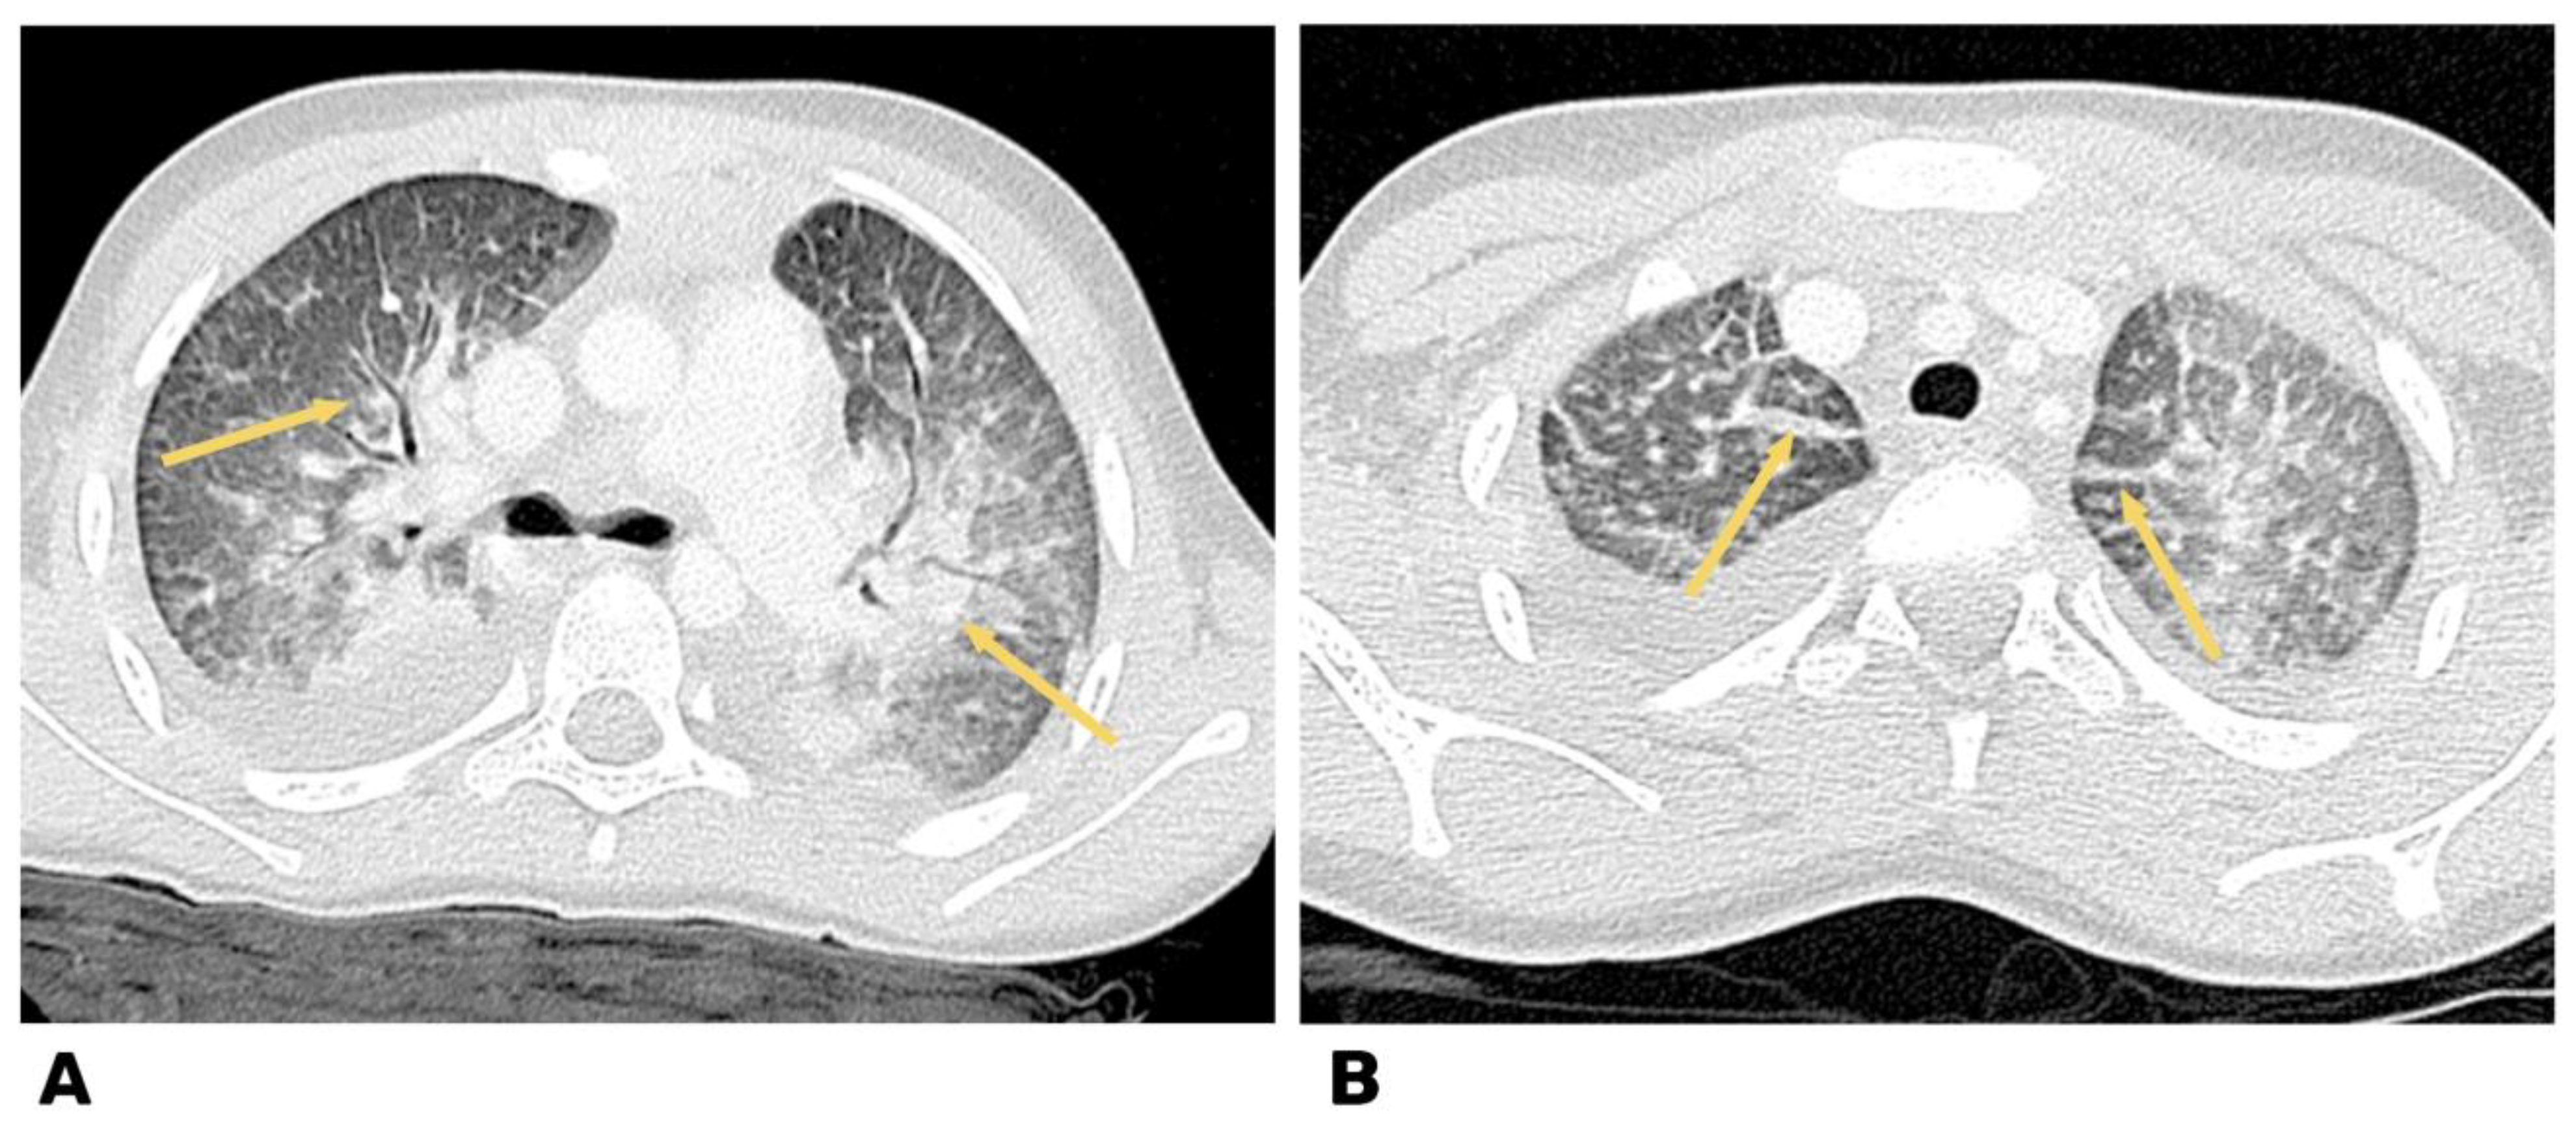

2. Case 1

2.1. Examination Data

2.2. Substantiation of Diagnosis

3. Case 2